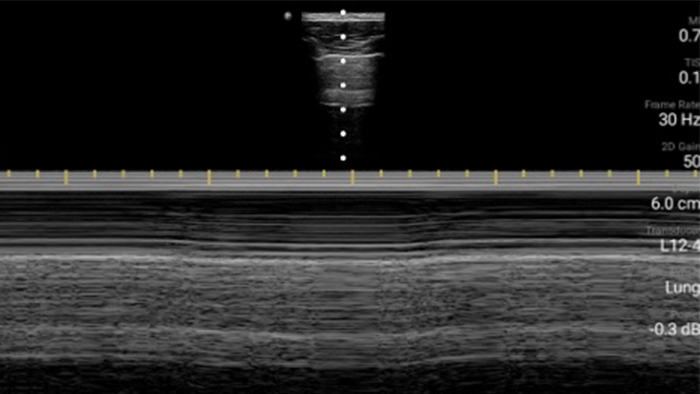

Congestief hartfalen is een groeiend probleem. Door echografie op uw praktijk te bieden, kan deze aandoening vroegtijdig worden ontdekt en de overlevingskansen aanzienlijk worden verbeterd.

Lumify kan helpen de subtiele details van een beeld zichtbaar te maken en afwijkende weefselstructuren bloot te leggen vanuit verschillende hoeken. Hierdoor kunt u met vertrouwen realtime beslissingen nemen, van diagnose tot herstel.

Beoordeling van de functie van het linkerventrikel